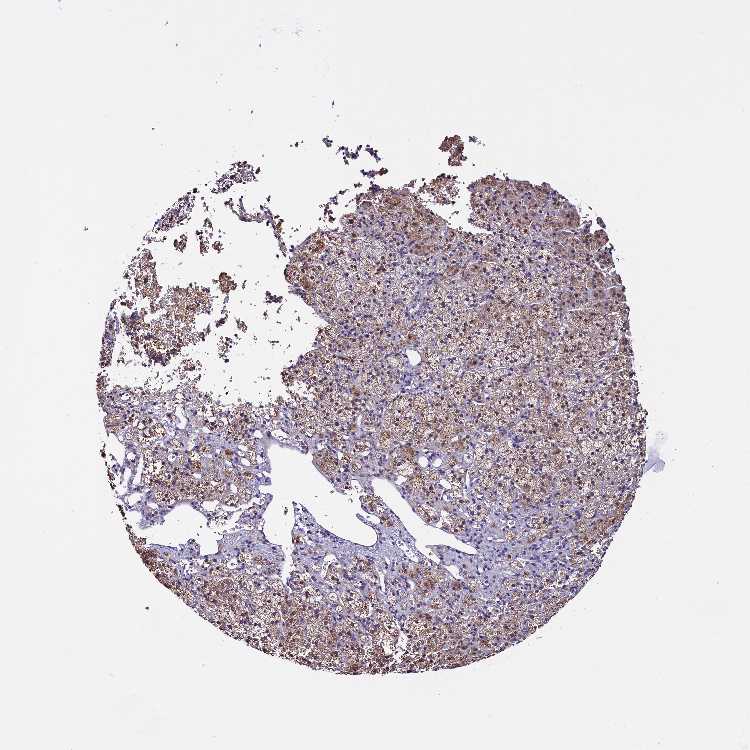

ADRENAL GLAND - Antibody stainingi

Antibody staining in the annotated cell types in the current human tissue is reported as not detected, low, medium, or high, based on conventional immunohistochemistry profiling in selected tissues. This score is based on the combination of the staining intensity and fraction of stained cells.

Each image is clickable and will lead to virtual microscopy that enables deeper exploration of all samples and also displays staining intensity scores, fraction scores and subcellular localization as well as patient and tissue information for each sample.

Antibody HPA041412Antibody HPA056006

Glandular cells MediumMedium